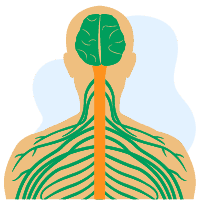

အာရုံကြောစနစ်မှာ ပင်မအာရုံကြောမကြီးလို့ခေါ်တဲ့ ဦးနှောက်နဲ့ ကျောရိုးအာရုံကြောမကြီးရယ်၊ သူတို့ကနေ ဖြာပြီးထွက်လာတဲ့ အာရုံကြောငယ်လေးတွေရယ်ဆိုပြီး ရှိပါတယ်။ ဒီအာရုံကြောလေးတွေမှာ ပြင်ပကလာတဲ့ အပူ၊ အအေး၊ တုန်ခါတာ၊ ထိသိတာကို ခံစားနိုင်တဲ့ အာရုံကြောတွေ ရှိသလို ဦးနှောက်က ပို့လွှတ်လိုက်တဲ့ လျှပ်စီးလှိုင်းတွေကို ကြွက်သားတွေကို ပို့ဆောင်ပေးနိုင်တဲ့ အာရုံကြောတွေရယ်ဆိုပြီး ရှိပါတယ်။ အာရုံကြောငယ်လေးတွေမှာ ဖြစ်တတ်တဲ့ ရောဂါဆိုတာ အာရုံကြောတွေမှာ ရောဂါတစ်ခုခုရှိနေရင် ဒါမှမဟုတ် တစ်ခုခုထိခိုက်သွားပြီဆိုရင် ပုံမှန်လုပ်နေကြအတိုင်း မလုပ်နိုင်တော့ပါဘူး။ ဥပမာ အာရုံကြောငယ်တစ်ချောင်း လုံးဝပျက်စီးသွားမယ်ဆိုရင် (ဒါမျိုး ဖြစ်တာ ရှားတော့ ရှားပေမယ့်) သူထောက်ပံ့ပေးနေတဲ့ ကြွက်သားက လှုပ်ရှားနိုင်မှာ မဟုတ်ပါဘူး။ သူက ဦးနှောက်နဲ့ ကြွက်သားကြားကို လျှပ်စီးကြောင်းကို အသယ်အပို့ လုပ်နေတာကိုး။ အများစုကတော့ လုံးလုံး ပျက်စီးတာမျိုး မဟုတ်ဘဲ အာရုံကြောအားနည်းတာ၊ ထိခိုက်တာကြောင့် ကြွက်သားတွေ အားပျော့တာလောက်ပဲ […]